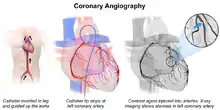

A coronary catheterization is a minimally invasive procedure to access the coronary circulation and blood filled chambers of the heart using a catheter. It is performed for both diagnostic and interventional (treatment) purposes.

Coronary catheterization is one of the several cardiology diagnostic tests and procedures. Specifically, through the injection of a liquid radiocontrast agent and illumination with X-rays,[1] angiocardiography allows the recognition of occlusion, stenosis, restenosis, thrombosis or aneurysmal enlargement of the coronary artery lumens; heart chamber size; heart muscle contraction performance; and some aspects of heart valve function. Important internal heart and lung blood pressures, not measurable from outside the body, can be accurately measured during the test. The relevant problems that the test deals with most commonly occur as a result of advanced atherosclerosis – atheroma activity within the wall of the coronary arteries. Less frequently, valvular, heart muscle, or arrhythmia issues are the primary focus of the test.

During coronary catheterization (often referred to as a cath by physicians), blood pressures are recorded and fluoroscopy (X-ray motion picture) shadow-grams of the blood inside the coronary arteries are recorded. In order to create the X-ray pictures, a physician guides a small tube-like device called a catheter, typically ~2.0 mm (6-French) in diameter, through the large arteries of the body until the tip is just within the opening of one of the coronary arteries. By design, the catheter is smaller than the lumen of the artery it is placed in; internal (intra-arterial) blood pressures are monitored through the catheter to verify that the catheter does not block blood flow (as indicated by "dampening" of the blood pressure).

The catheter is itself designed to be radiodense for visibility and it allows a clear, watery, blood compatible radiocontrast agent, commonly called an X-ray dye, to be selectively injected and mixed with the blood flowing within the artery. Typically 3–8 cc of the radiocontrast agent is injected for each image to make the blood flow visible for about 3–5 seconds as the radiocontrast agent is rapidly washed away into the coronary capillaries and then coronary veins. Without the X-ray dye injection, the blood and surrounding heart tissues appear, on X-ray, as only a mildly-shape-changing, otherwise uniform water density mass; no details of the blood and internal organ structure are discernible. The radiocontrast within the blood allows visualization of the blood flow within the arteries or heart chambers, depending on where it is injected.